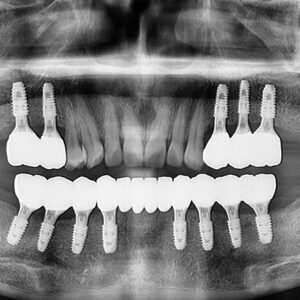

울산무통치과 틀니가 불편하다면 안녕하세요. 울산무통치과 뉴욕연합치과입니다. 고령화 사회에 진입 후 사람들의 관심사는 얼마나 건강하고 행복하게 사느냐에 맞춰져 있는데 사람의 오복 중 하나인 치아, 건강한 치아는 삶의 질을 높여주고…

울산무통치과 고민중이시라면 안녕하세요. 울산무통치과 뉴욕연합치과입니다. 나이가 들면서 자연스럽게 신체의 모든 부위의 기능들이 노화를 겪게 되는데, 그중 치아도 유기적인 신체의 부위 중 하나로 노년기가 되면서 치아의 기능이 상실되는 경우가…

울산무통치과 치조골이 부족하더라도 안녕하세요. 울산무통치과 뉴욕연합치과입니다. 시대가 변하고 사람들의 수명이 늘어나면서 고령화 시대가 진행되고 있는데요. 나이가 들어 노화가 진행될수록 약해지는 구강 건강으로 인해 올바른 치아 관리에 대한 관심도 높아지고…